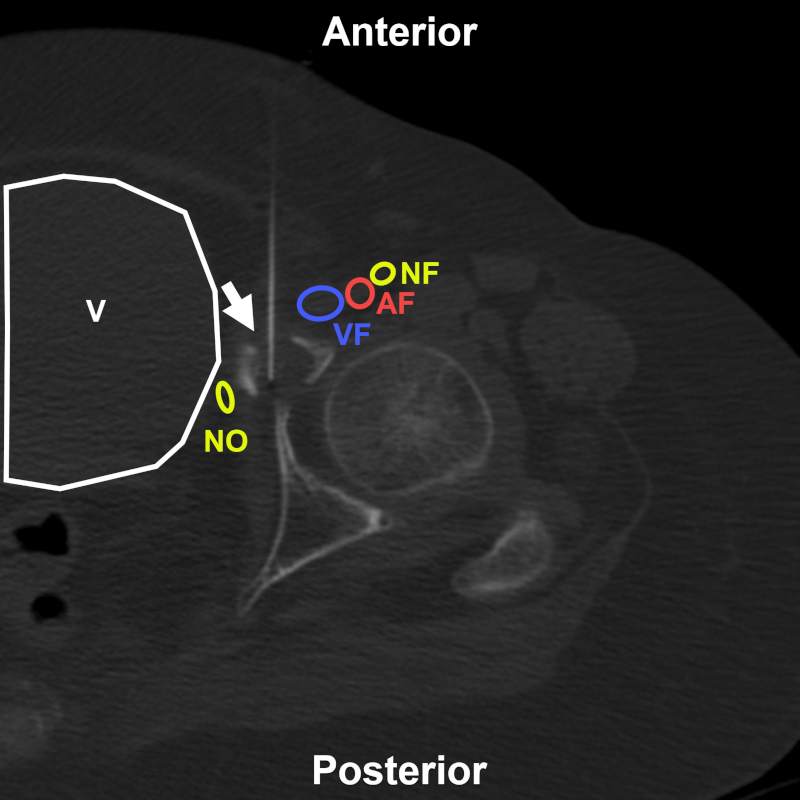

Mujer de 74 años en estudio por fractura patológica acetabular izquierda. BP con abordaje directo anterior (flecha) bajo TC. Estructuras a evitar: AF: arteria femoral; VF: vena femoral; NF: nervio femoral; NO: nervio obturador; V: vejiga. Aguja utilizada: Franseen 20 G. Diagnóstico final: cambios reparativos y elementos correspondientes a quiste óseo simple.

Figura 10